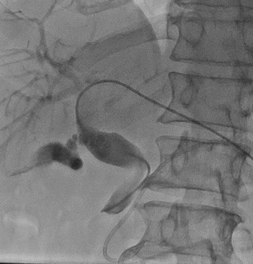

内镜逆行插管仅进入胰管,胆总管下段闭塞,插管不成功;内镜下放置胰管支架。 | |

经皮经肝胆道穿刺顺行疏通胆总管 |

胆管支架放置成功,造影剂顺利经支架流入肠道 |